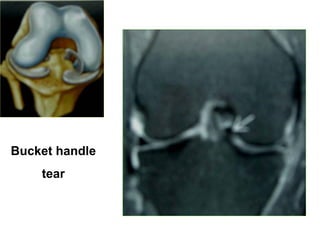

Bucket handle tear

Bucket handle

tear